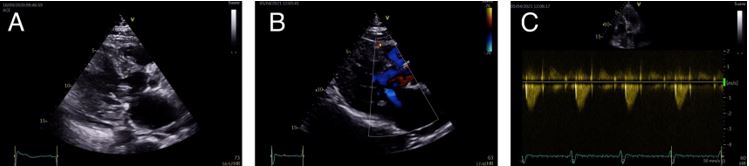

The progressive improvement of the patient and the resolution of the septic condition allowed the gradual weaning of ventilatory and vasoactive support. During the recovery in the cardiology ward, the patient underwent respiratory and physical rehabilitation. At discharge, 38 days after admission, the echocardiogram showed a thinned anterior ventricular septum (7 mm) and a complete resolution of dynamic LVOTO (peak gradient of 19 mmHg with Valsalva manoeuvre). Left ventricle systolic function remain normal. At one year of follow-up, the patient remained without LVOTO with bisoprolol 5mg bid, and in NYHA functional class II/IV.

Fig 4 CC - Clinical Case - hypertrophic cardiomyopathy.jpg